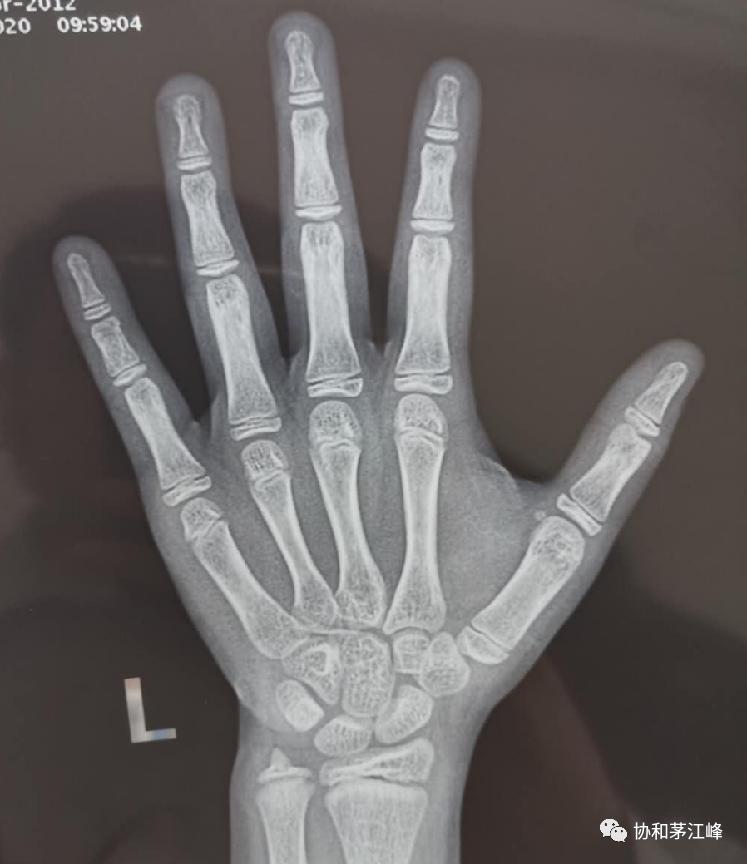

患者虽然在同龄儿童中身材偏高,但由于受到女性激素的影响,骨龄已达11岁。这提示,再过1-2年,骨骺就会关闭。患者预计终身高约 148-150 cm。听了这话,患者父母都倒吸一口凉气。“150cm,对一个女性而言,似乎有点矮了。”

骨龄11岁,有图有真相